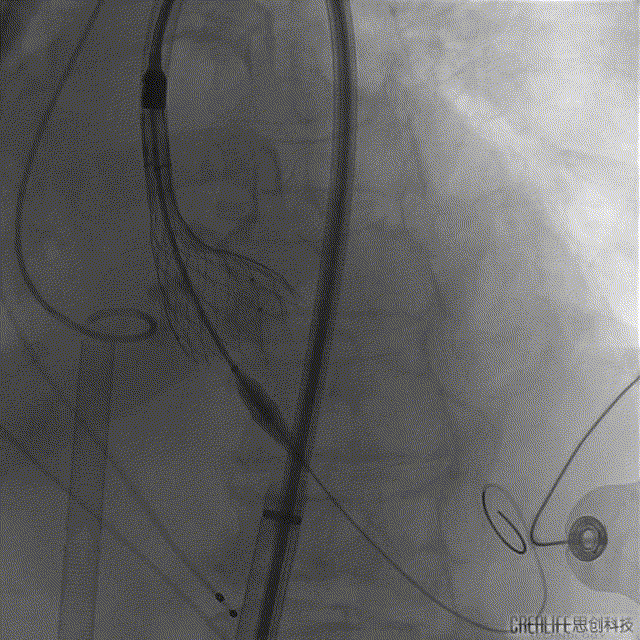

手术过程

冠脉PCI术前影像

冠脉PCI术后影像

主动脉根部造影

球囊扩张

瓣膜定位

瓣膜释放

球囊后扩

瓣膜置入后影像评估